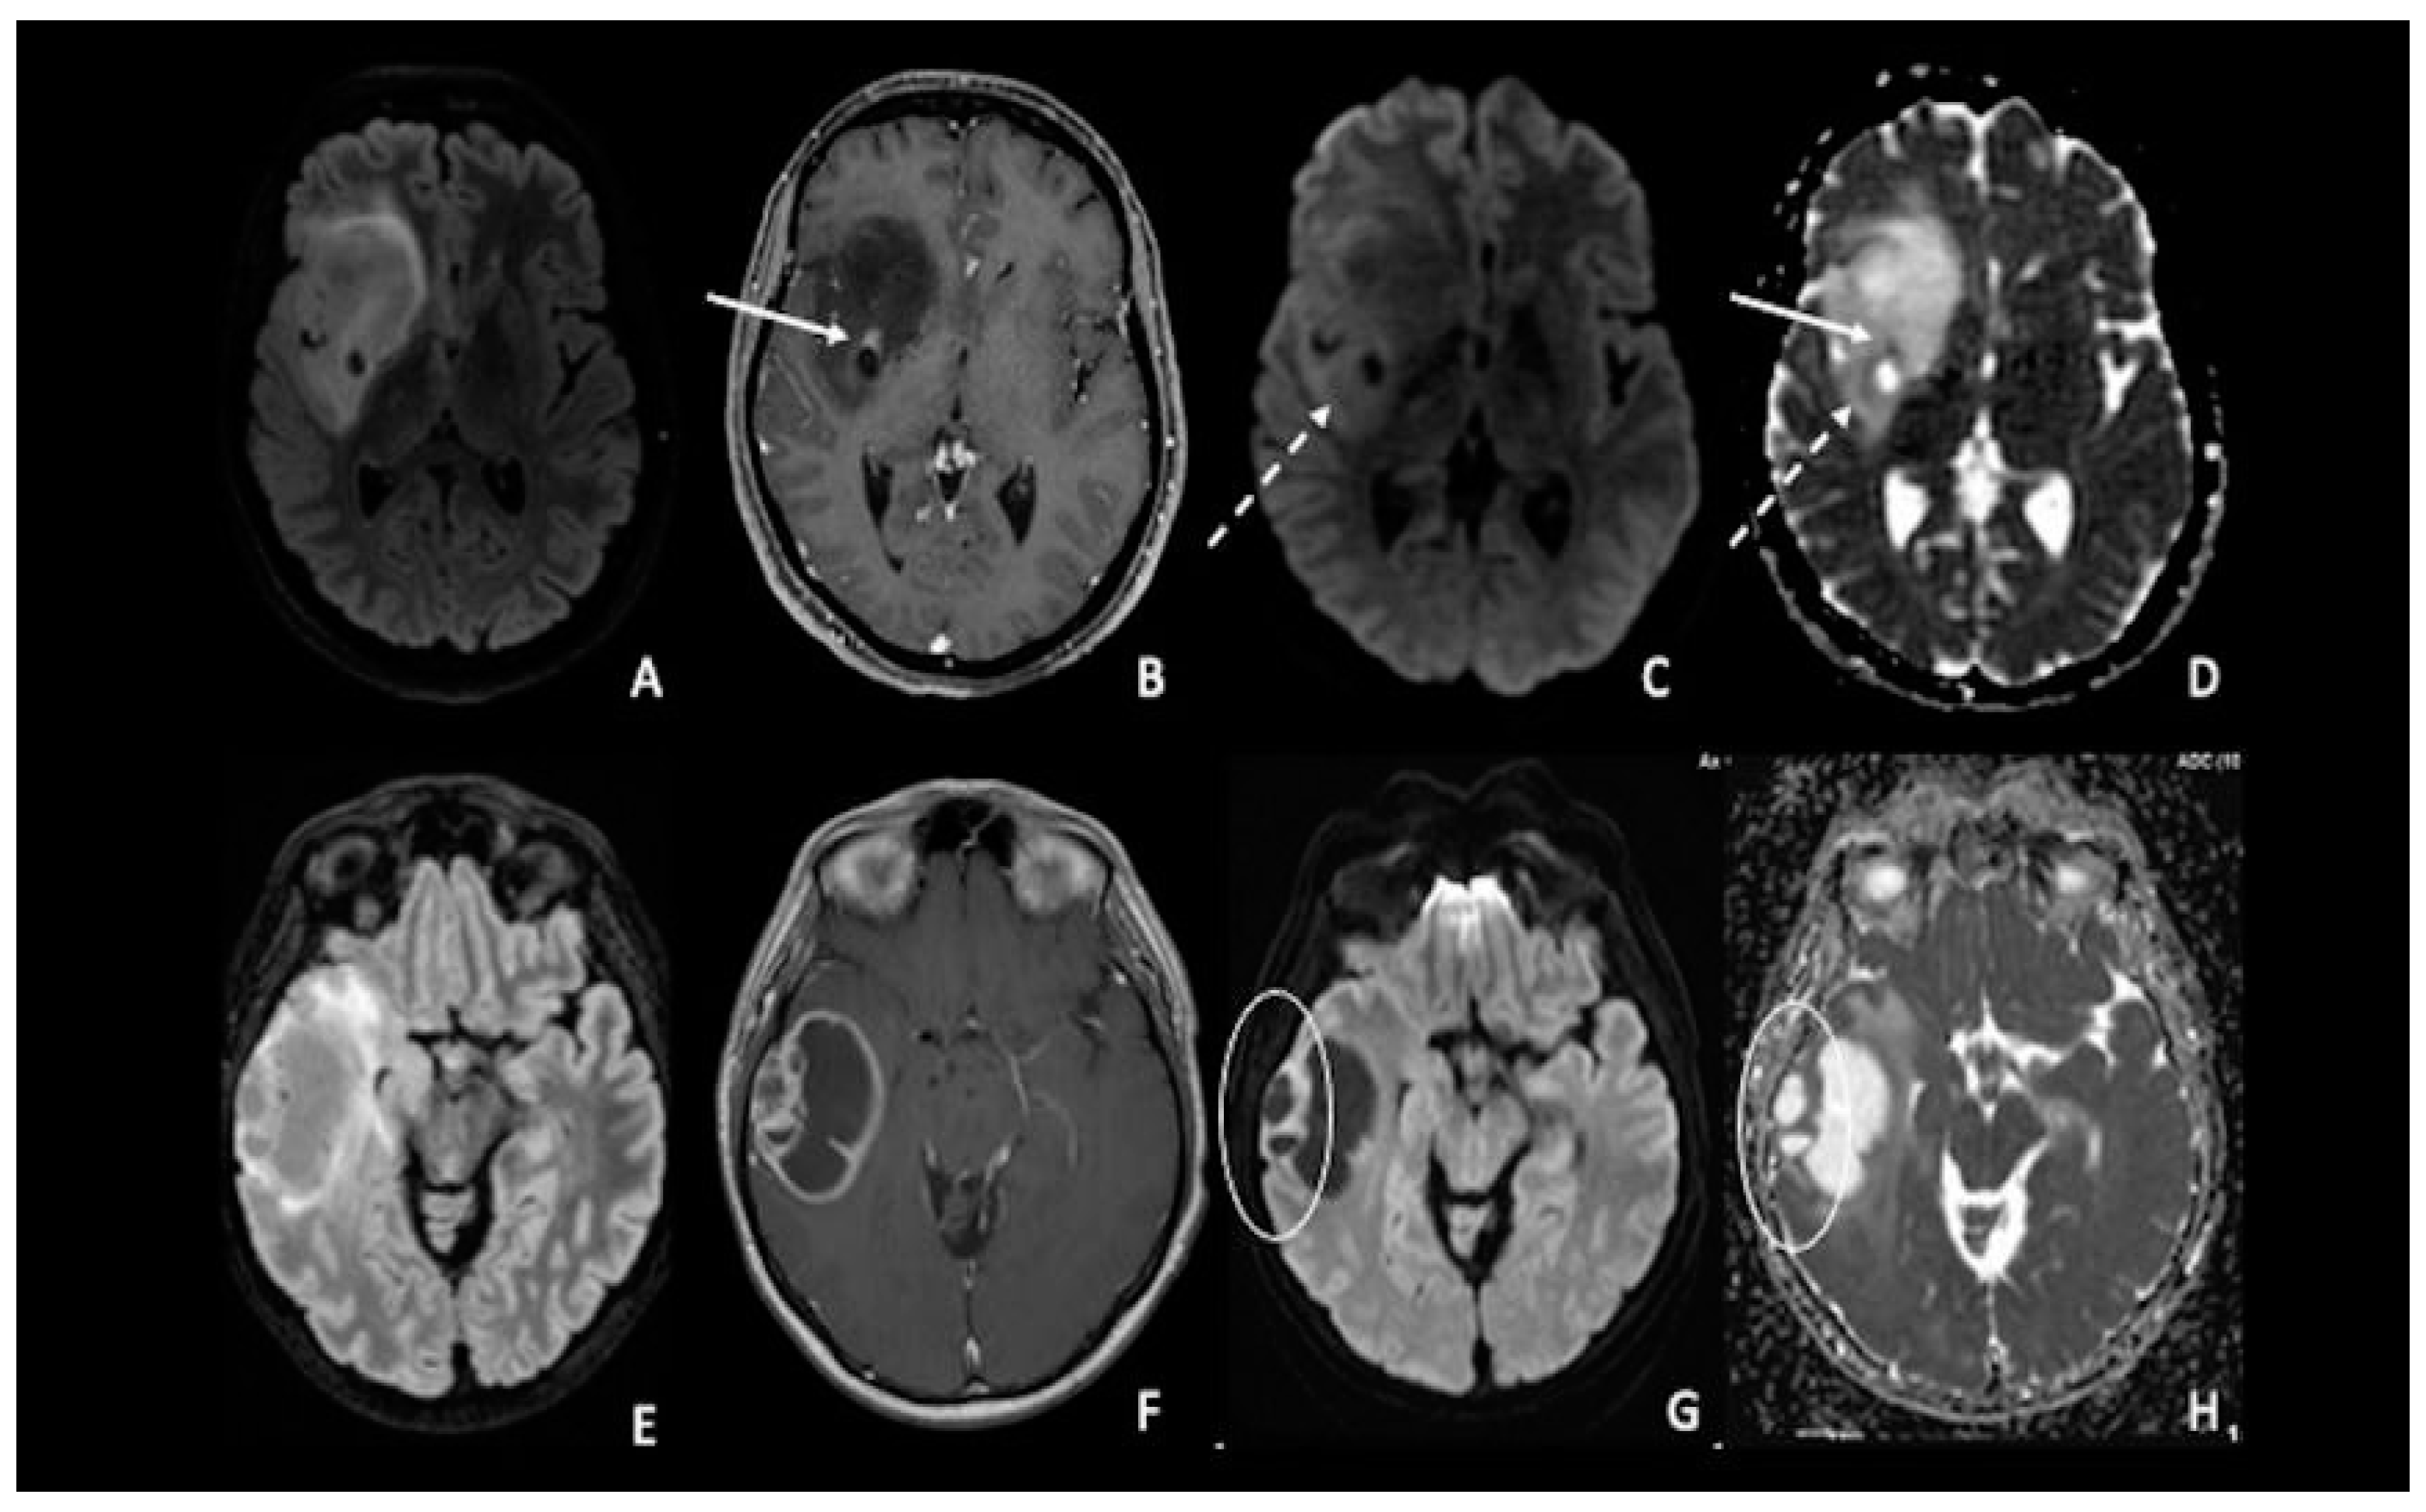

4. Lymphomas

5. Medulloblastomas

7. Metastasis

8. Gliomas vs. Metastasis